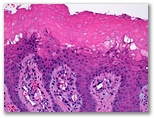

Granuloma piogenico

Panadizo herpético ulcerado

Ectima contagioso (Orf)